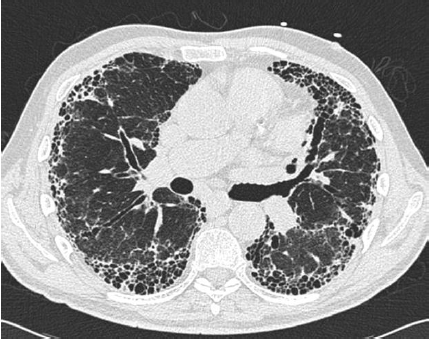

A tomografia computadorizada de alta resolução é de grande ajuda no diagnóstico das doenças pulmonares. O principal diagnóstico relacionado à imagem abaixo é: